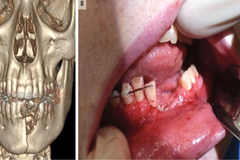

Khi đang hút thuốc lá điện tử, không may điếu thuốc phát nổ khiến cậu bé 17 tuổi bị gãy đôi xương hàm, bay mất răng và mồm không thể khép lại.